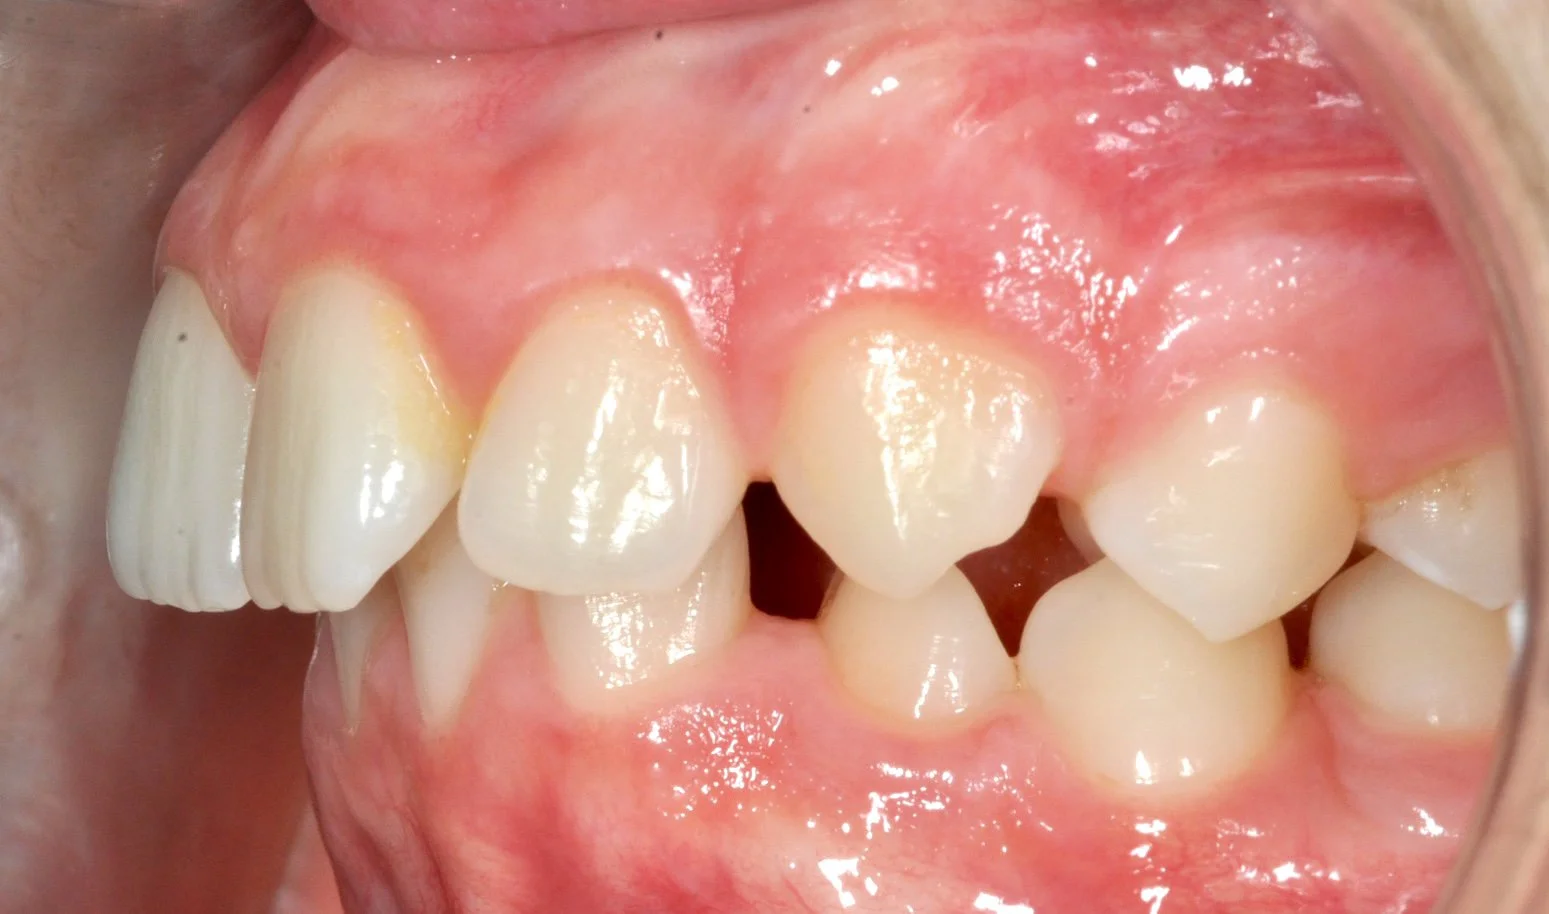

Caso 1 – Allineatori trasparenti in età evolutiva

Giovane paziente in fase di crescita con denti superiori troppo in avanti rispetto agli inferiori, arcate strette e rotazioni importanti di alcuni elementi.

Grazie al trattamento con allineatori trasparenti, in 18 mesi è stato possibile accompagnare la crescita, correggere l’allineamento dei denti e migliorare il rapporto tra le arcate, ottenendo un sorriso più armonioso e funzionale.

PRIMA

DOPO